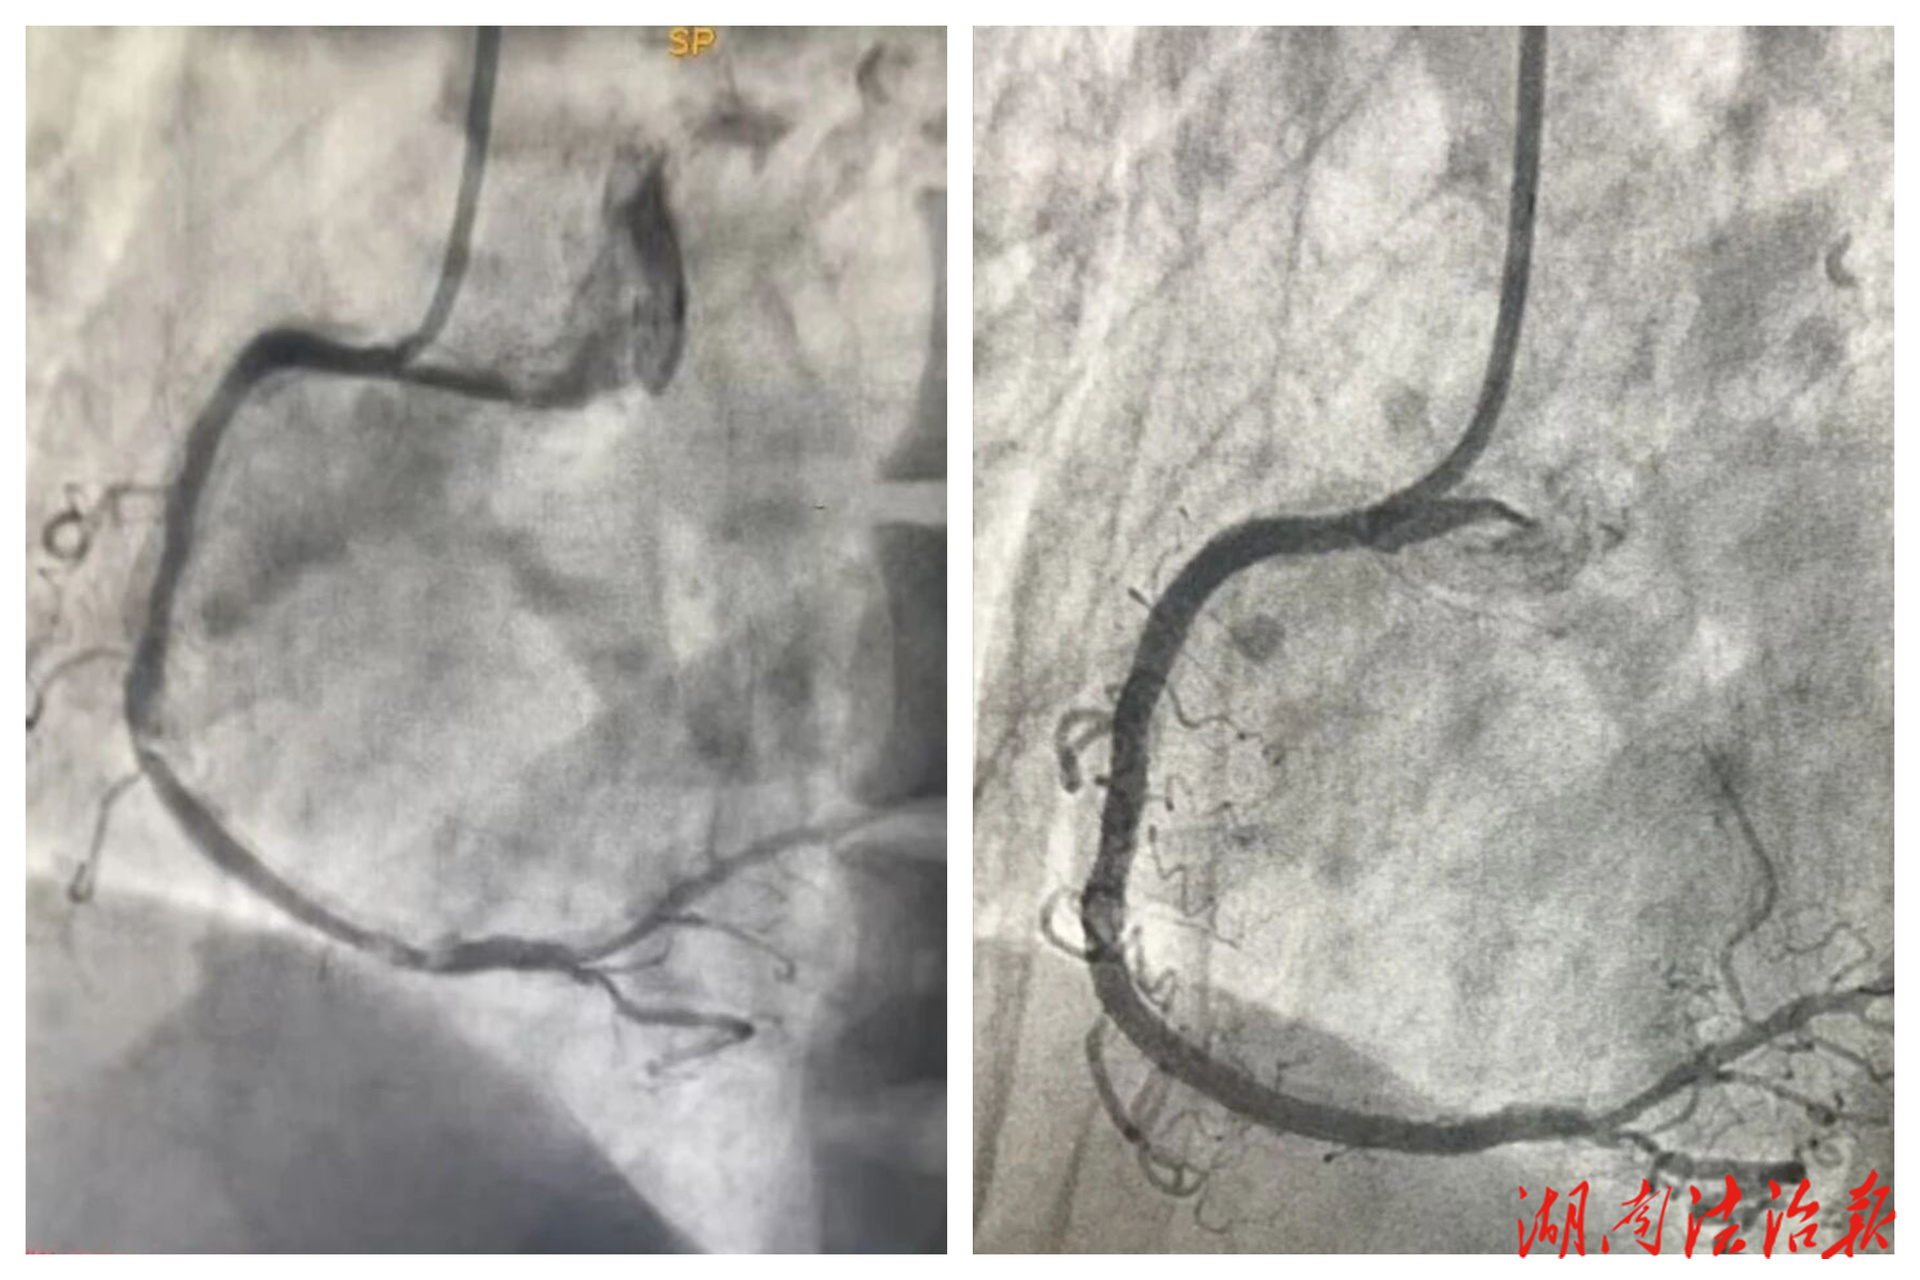

46岁的唐女士确诊尿毒症多年,近一个月反复胸痛,病情严重。经冠脉造影检查,发现其右冠状动脉中段存在95%的重度狭窄,并伴有严重钙化——血管壁如同被坚硬“石头”包裹,常规介入手术难以进行。若不及时处理,患者随时可能发生急性心肌梗死,危及生命。

手术中,湘雅二医院专家与本院胸痛中心团队紧密协作,将直径仅1.25毫米的橄榄型旋磨头送至病变血管处。旋磨头以每分钟约12-15万转的高速旋转,遵循“只磨硬、不伤软”的原则,将钙化斑块精细研磨成微颗粒,后由人体自然代谢清除。术中患者一度出现血压、心率下降,经团队迅速应对后转危为安。旋磨完成后,团队顺利植入支架,成功开通血管,恢复血流。

手术前、后对比图